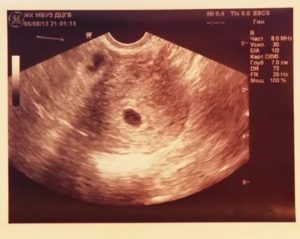

Какой срок позволяет увидеть плодное яйцо и определить его размеры? Увидеть эмбрион можно, когда плодное яйцо будет не менее 1 см. Если произошла задержка менструального кровотечения на неделю, к этому времени процесс гестации ориентировочно достиг 6 недель.

К этому периоду при диагностике высокоточным аппаратом плодное яйцо уже видно. Определить наличие сердцебиение эмбриона и рассмотреть его строение пока невозможно.

В 6 недель вынашивания эмбриона при проведении ультразвукового исследования на фоне утолщенного гиперэхогенного эндометрия определяется плодное яйцо. Оно представляет собой округлое или овальное анэхогенное образование с гиперэхогенным ободком.

Внутренний диаметр плодного яйца в этом сроке составляет порядка 22 миллиметров. Начиная с 5 недель беременности его размер увеличивается на 1-2 мм.

В плодном яйце уже должны визуализироваться эмбрион и желточный мешок. Располагаясь эксцентрично, они формируют изображение на мониторе в виде двойного пузырька. Желточный мешок определяется как округлое тонкостенное образование с анэхогенным содержимым внутри.

Его нормальная величина составляет 3-5 мм в диаметре. Функцией этого образования является питание эмбриона до тех пор, пока не сформируется плацента, которая займётся этим.

Главным и пока единственным измеряемым размером плода является копчико-теменной размер. В 6 недель он составляет 6 миллиметров. КТР равен длине эмбриона от головки до копчика.